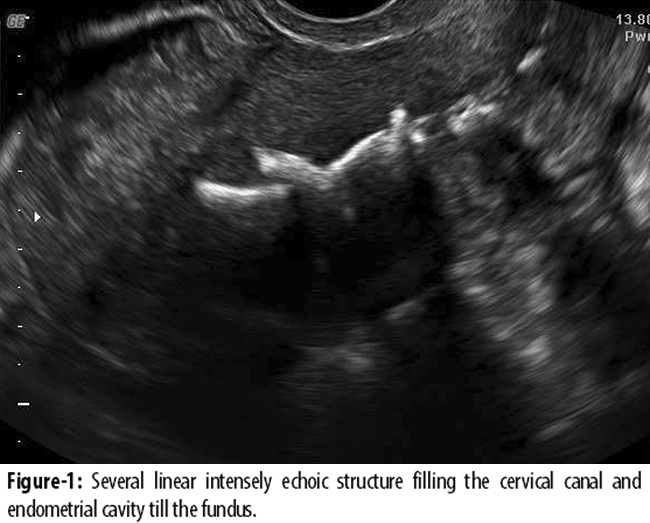

A 26-year-old multiparous woman was referred to our department with irregular vaginal bleeding, lower abdominal pain and chronic vaginal discharge. She had a history of induced abortion three years ago. She described an unsafe abortion episode. Her medical history revealed irregular menstrual cycles and minimal dysmenorrhoea for a year. She repeatedly approached her family physician with chronic vaginal discharge complaint. She had been empirically treated for vaginitis and pelvic infection. None of these treatments were based on a documented cause of PID or sexually transmitted disease (STD). She had never been evaluated with pelvic or transvaginal ultrasonography after abortion. Her first general physical and pelvic examinations were performed in our hospital. On pelvic examination, the uterus was normal in size and position. The uterine and adnexal tenderness, and purulent vaginal discharge suggestive of PID was detected on pelvic exam. Transvaginal ultrasound revealed several linear intensely hyperechoic structure filling the cervical canal and endometrial cavity till the fundus and minimal fluid collection was detected in the Pouch of Douglas (Figure-1).